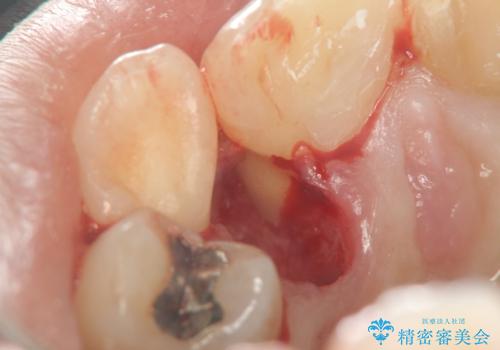

X線写真より、充填剤の突き出た状態の根管治療の再治療を行い、セラミック治療を計画すると同時に、

歯ブラシがしづらく虫歯の原因となっている歯の位置の悪い右上側切歯の抜去を行います。

清掃を難しくしている歯を抜去することで虫歯の再発を防ぐような治療方針としました。